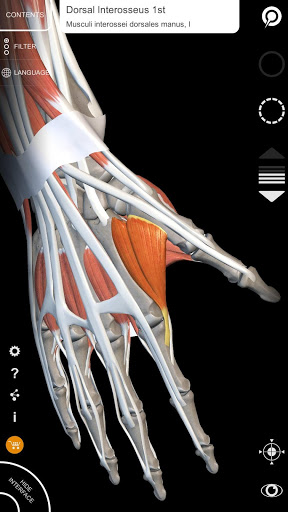

"Anatomy 3D Atlas" vous permet d'étudier l'anatomie humaine de manière simple et interactive.

Grâce à une interface simple et intuitive, il est possible d'observer chaque structure anatomique sous n'importe quel angle.

Les modèles anatomiques 3D sont particulièrement détaillés et avec des textures jusqu'à une résolution de 4k.

• Visualisation des muscles à travers des niveaux de couches depuis les plus superficielles jusqu'aux plus profondes

• En sélectionnant un modèle ou une épingle, le terme anatomique associé apparaît

• Description des muscles : origine, insertion, innervation et action